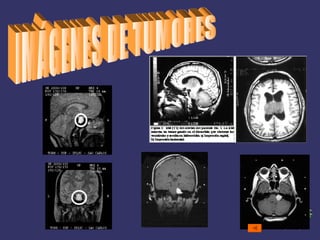

IMÁGENES DE TUMORES Atrás

Técnicas y Medios de Diagnósticos Estudios radiológicos : - tomografía - resonancia magnética Biopsia Estudio del líquido cefalorraquideo Electroencefalograma Estudio de niveles hormonales Determinación de marcadores tumorales